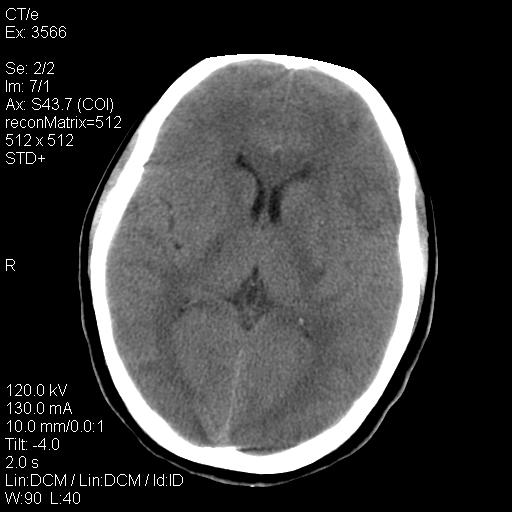

标题: CT9947:女,20岁,妊娠9个月,突然癫痫症状 [打印本页]

标题: CT9947:女,20岁,妊娠9个月,突然癫痫症状

双侧脑白质缺血缺氧性改变,并高度可疑“蛛网膜下腔出血”。

后可复性脑病,

考虑 妊娠子痫或妊高征

双侧脑白质缺血缺氧性改变.

考虑先兆子痫\\子痫致he,建议mri除外有无合并静脉窦血栓形成.

考虑pres

的确应该考虑可逆性后部脑病综合症--pres。感谢天南地北老师的指引,又学了一招儿,开心,呵呵!

考虑可逆性后部脑病综合症

支持pres